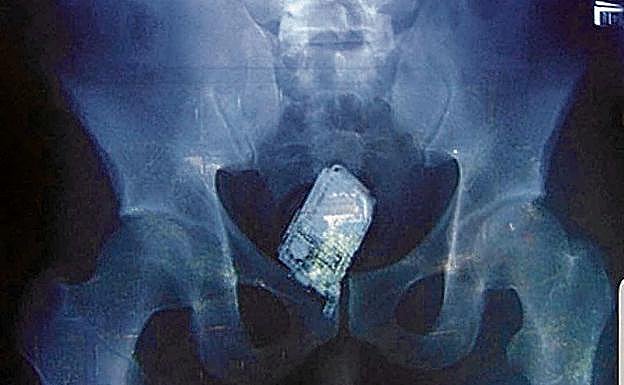

Drones, estiletes, móviles en el ano y droga en folios: el coladero de las cárceles españolas

El escándalo de la prisión de Brieva (Ávila), donde se investiga a dos trabajadores por proporcionar móviles y otros favores a cambio de sexo a ... Ana Julia Quezada, la asesina del pequeño Gabriel (Níjar, 2018), ha puesto en entredicho la seguridad en las cárceles españolas, sobre las que orbita una idea: todo se compra y todo se vende. Sólo hace falta fijar el precio y estar dispuesto a pagarlo.